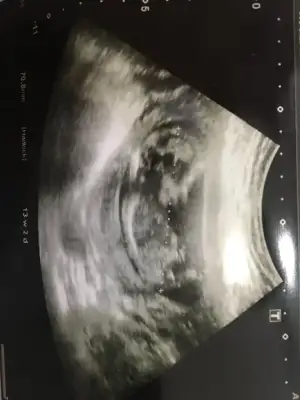

dr soylemeden siz gorun genital nub teorisi ( bebegin cinsiyeti)

Arkadaşlar lutfen tahmin eder misiniz

Kızlar benim nub teorisi tuttu kızım olacak inşallah 🤗 Bu ara isim arayışındayız isim önerileriniz varsa alırım valla 😍

Öyle konu açılmıştı ama hepsi tutmadı 😊 kese degilde yolksac tutuyor kese belirlemez cinsiyeti 😬😕 kesenizi paylaşın yolksacı çizim 😉